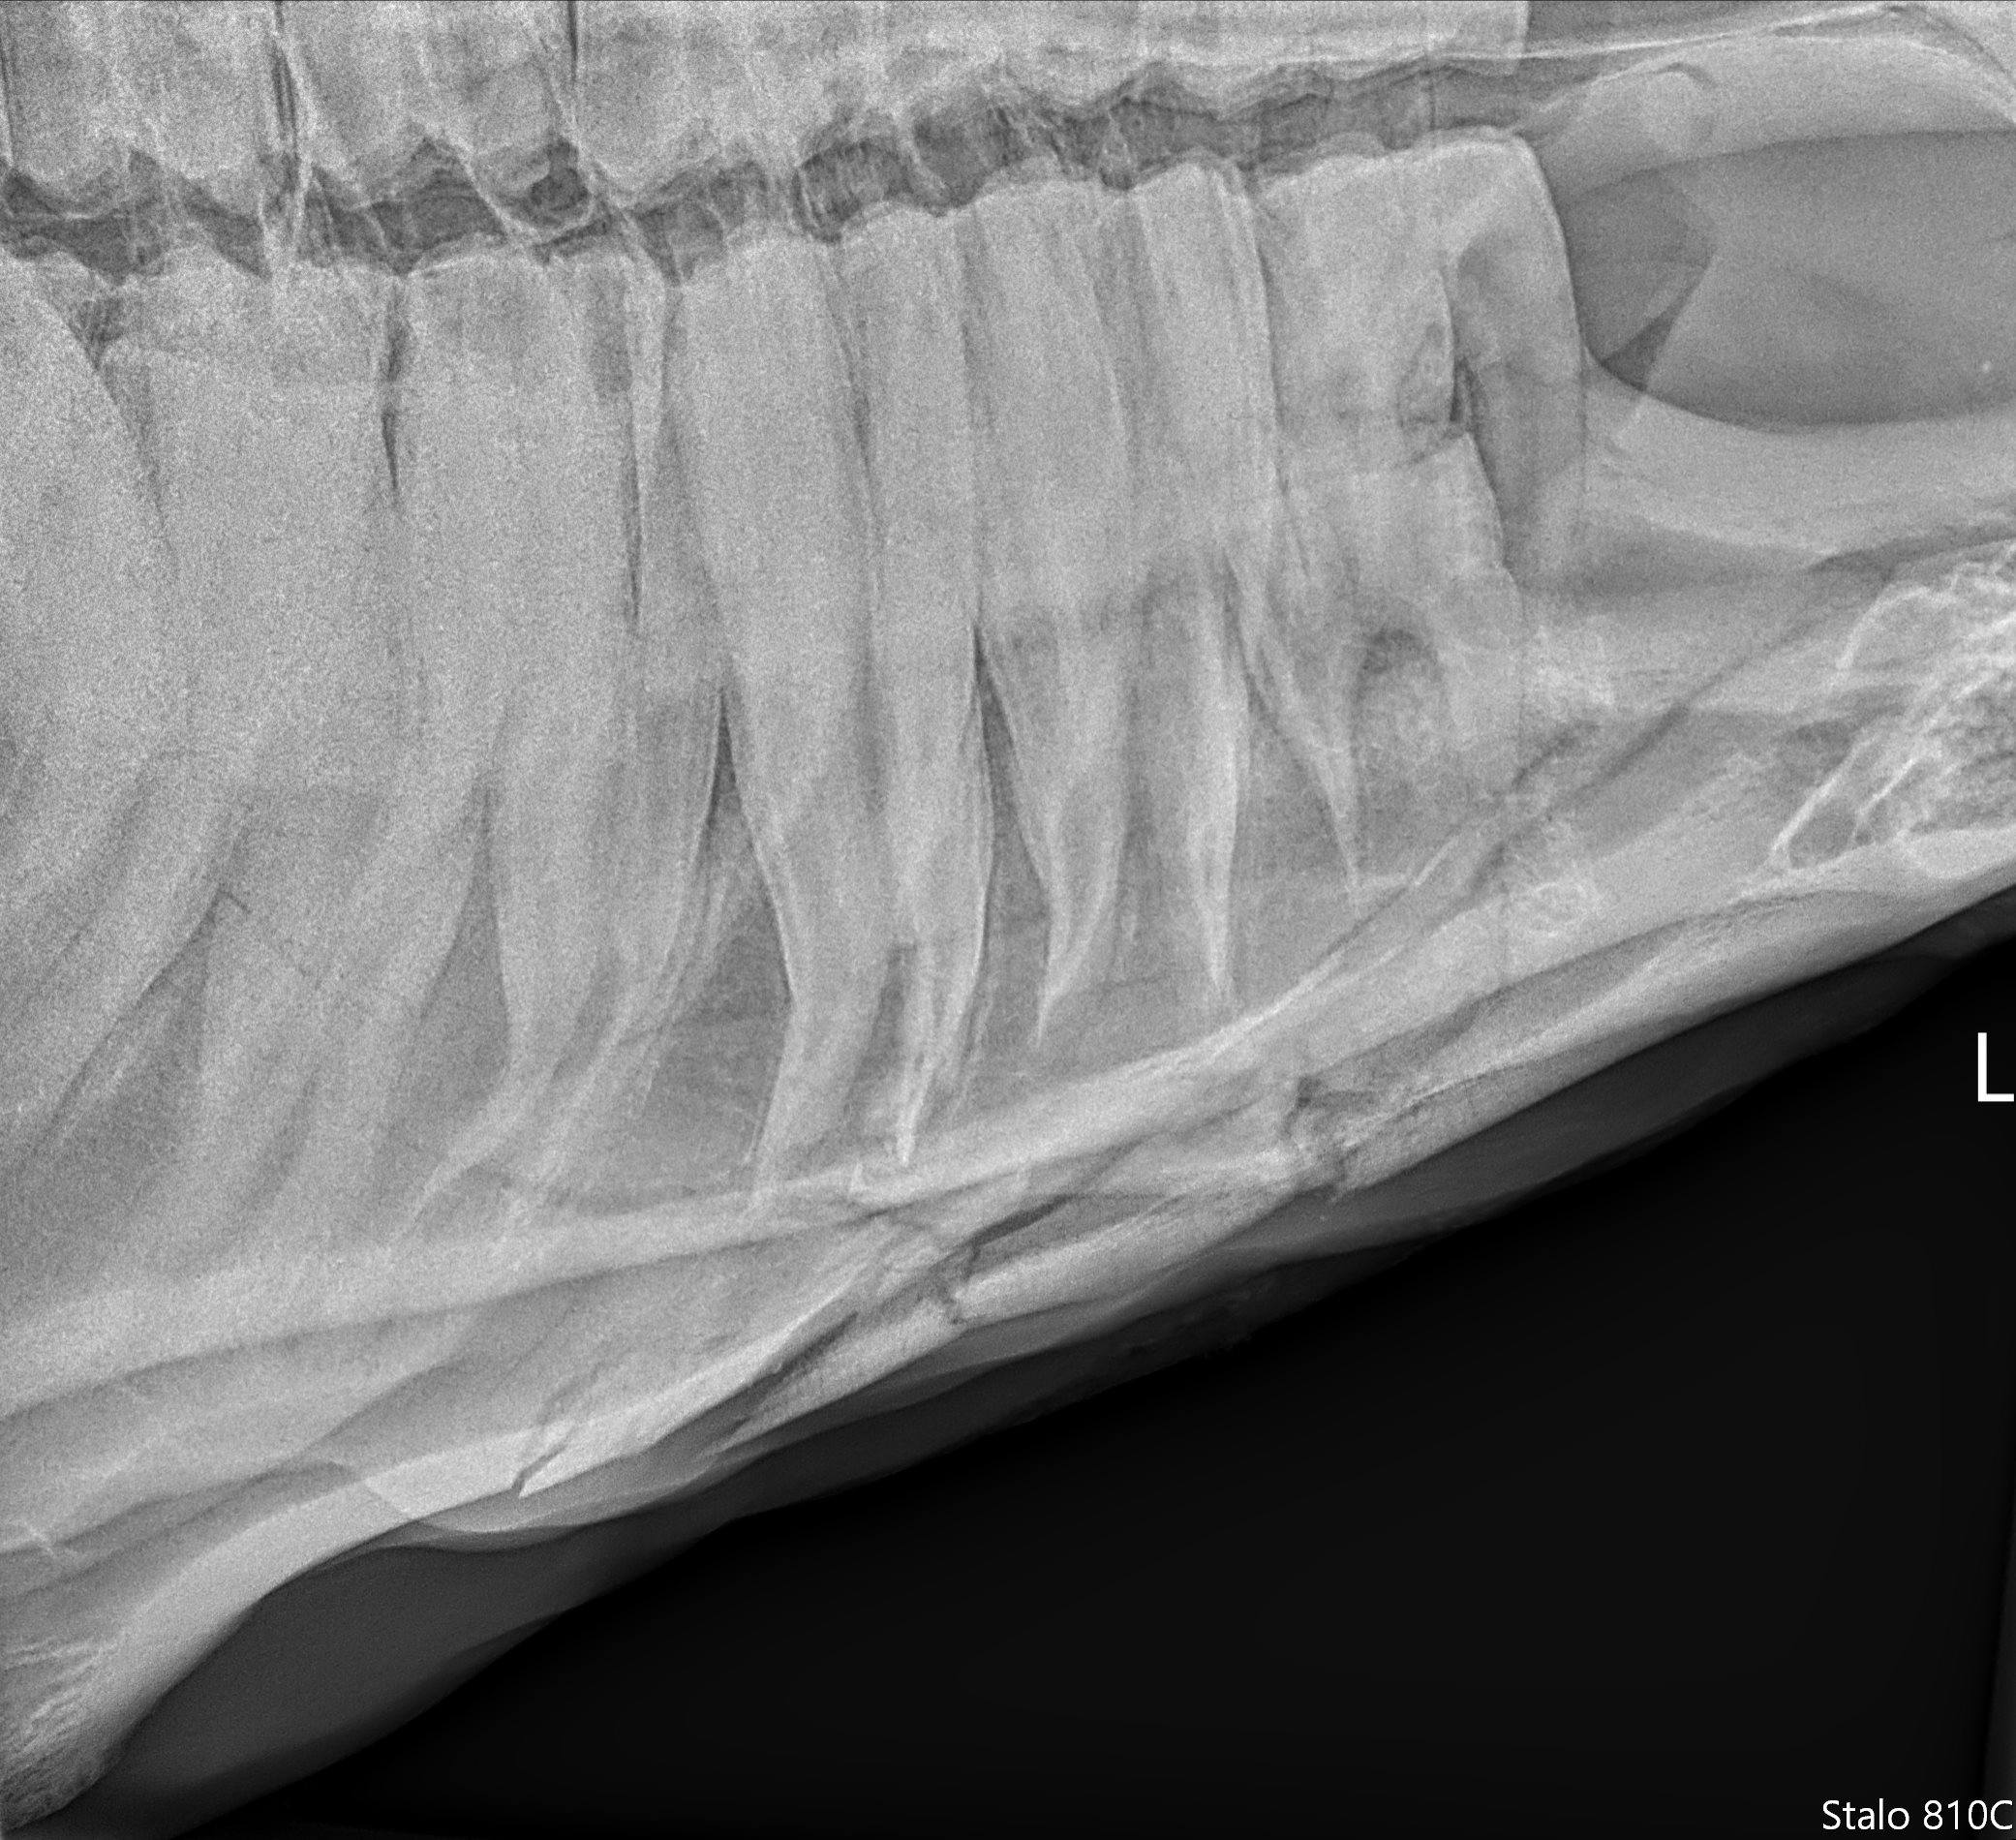

Dental radiographs are an essential part of determining if teeth need to be extracted, to help predict how difficult a tooth may be to extract, and to monitor teeth with minor issues/fractures.